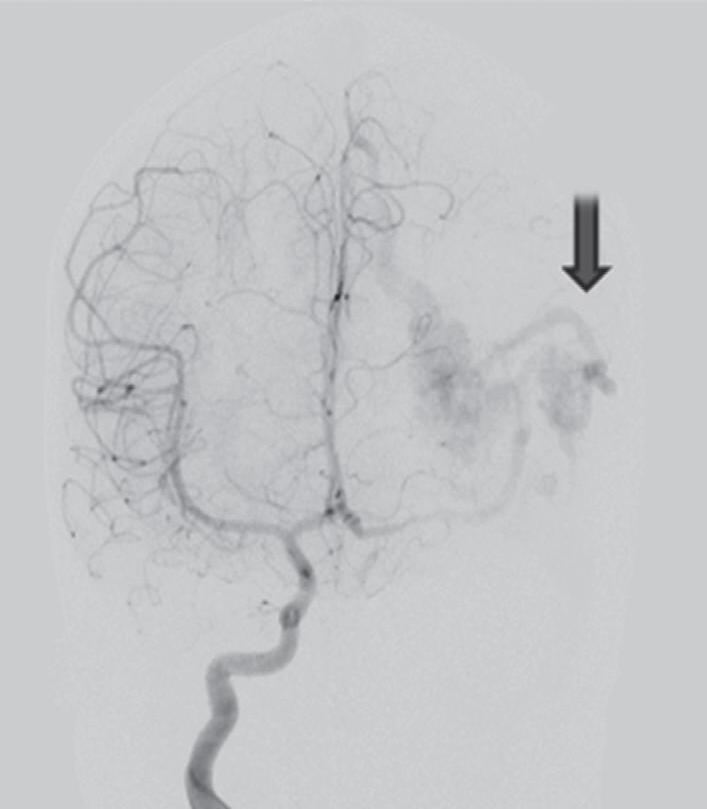

Fig. 1-16. RNM encéfalo T1 com contraste: (a) Coronal e (b) axial demonstrando MAV grau 4 frontoparietal esquerda. (c,d) Arteriografia cerebral AP mostrando a irrigação pelos ramos da cerebral anterior e média esquerda, além da cerebral anterior direita, com drenagem superficial para o seio sagital superior. Seta azul apontando para o nidus da MAV.